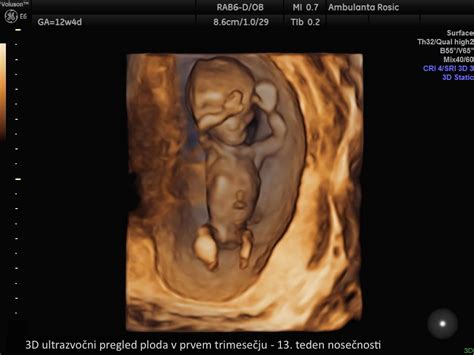

Pregledi v prvem trimestru vključujejo laboratorijske analize krvne slike, krvnega sladkorja na tešče, krvne skupine in RH faktorja, test na toksoplazmo gondi in sifilis, ultrazvočno potrditev nosečnosti do 11. tedna in pregled nuhalne svetline (ki ga stroka priporoča), ki se opravi med 11. in 14. tednom nosečnosti.

- Prvo trimesečje: Vključuje laboratorijske analize (krvna slika, krvni sladkor, krvna skupina, Rh faktor, testi na toksoplazmo in sifilis), ultrazvočno potrditev nosečnosti do 11. tedna ter pregled nuhalne svetline med 11. in 14. tednom, ki ocenjuje tveganje za kromosomske nepravilnosti.